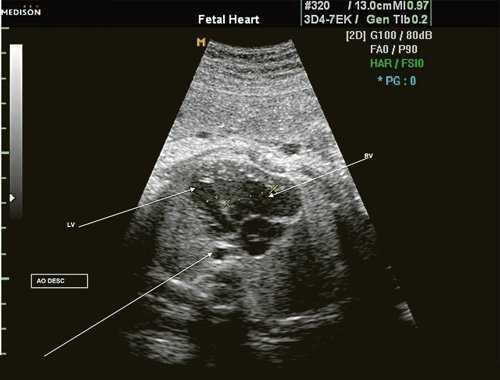

Исходя из особенностей внутрисердечной гемодинамики плода, для диагностики коарктации аорты были предложены косвенные признаки патологии в антенатальном периоде: дилатация правого желудочка и его гипертрофия (см. рис. 3), дилатация легочной артерии [6, 7, 14]. Авторы считают, что это достоверные признаки и встречаются они достаточно часто (в 18 из 24 случаев верифицированных диагнозов коарктации аорты). Поэтому была предложена оценка индексов отношения полости правого желудочка к левому (в норме - 1,1) и легочной артерии к аорте (у здоровых - 1,2). Исходя из увеличения этих параметров, можно предположить наличие затрудненного выброса в аорту или гипоплазию дуги аорты. Тем не менее, по данным предложивших эти косвенные признаки авторов, такие изменения выявляются только в 30% наблюдений (рис. 4).

Рис. 4. Диспропорция размеров желудочков сердца при коарктации аорты. RV - правый желудочек; LV - левый желудочек; AO DESC - поперечное сечение нисходящего отдела аорты.